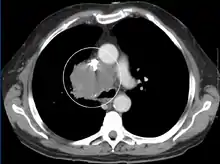

The main techniques of diagnosing SVCS are with chest X-rays (CXR), CT scans, transbronchial needle aspiration at bronchoscopy and mediastinoscopy.[5] CXRs often provide the ability to show mediastinal widening and may show the presenting primary cause of SVCS.[5] However, 16% of people with SVC syndrome have a normal chest X-ray. CT scans should be contrast enhanced and be taken on the neck, chest, lower abdomen, and pelvis.[5] They may also show the underlying cause and the extent to which the disease has progressed.[5]